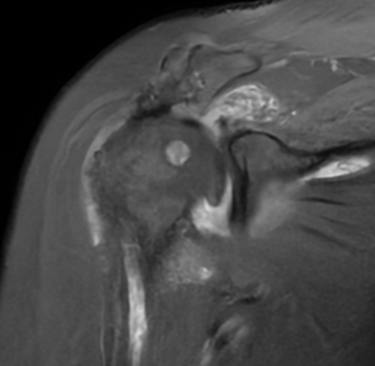

👉 En las imágenes de resonancia magnética se observa la ausencia o retracción severa de los tendones del manguito rotador, lo que impide una reparación convencional.